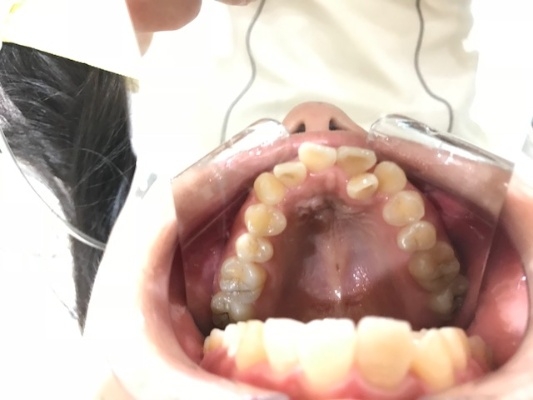

上顎